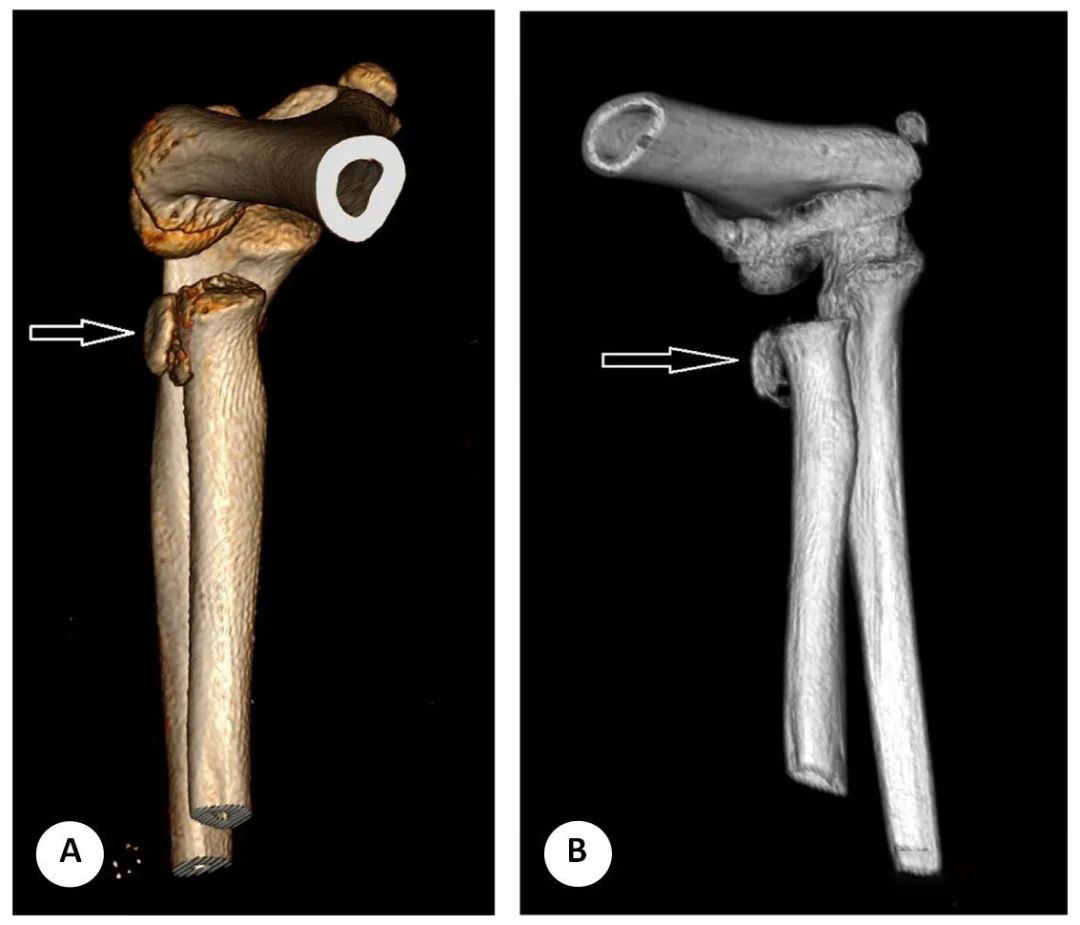

图 10 (A、B) 获得此 CT 用于手术计划,并根据肘关节轴位薄层 CT 重建三维重建。这名 8 岁的病人表现为近端桡骨严重移位的 Salter-Harris II 型骨折。术前肘关节 CT 显示桡骨近端骨骺翻转移位 270 度 (箭头所指)。